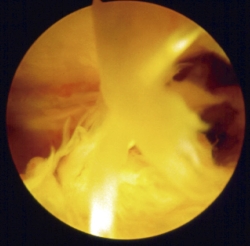

Siguiendo por los recesos lateral y medial (Figura 5) se llega a la zona suprapatelar, cuya fibrosis es la primera causa de limitación de la flexión (Figura 6). En este espacio hay que ser muy meticuloso para resecar con motor (Figura 7) y radiofrecuencia las adherencias, los nódulos, cíclopes (Figura 8), la fascia profunda del cuádriceps, con esqueletización de la cara anterior de fémur si es necesario, y liberar el alerón externo e interno, en función de la rótula: si está lateralizada (liberación solo lateral) o bien centrada (liberación lateral y medial), para facilitar el recorrido rotuliano. La limpieza de este espacio es fundamental para recuperar el máximo grado de flexión.

Figura 8. Nódulo fibroso entre polo superior de rótula y tendón cuadricipital. Resalte y dolor en prótesis con estabilización posterior.